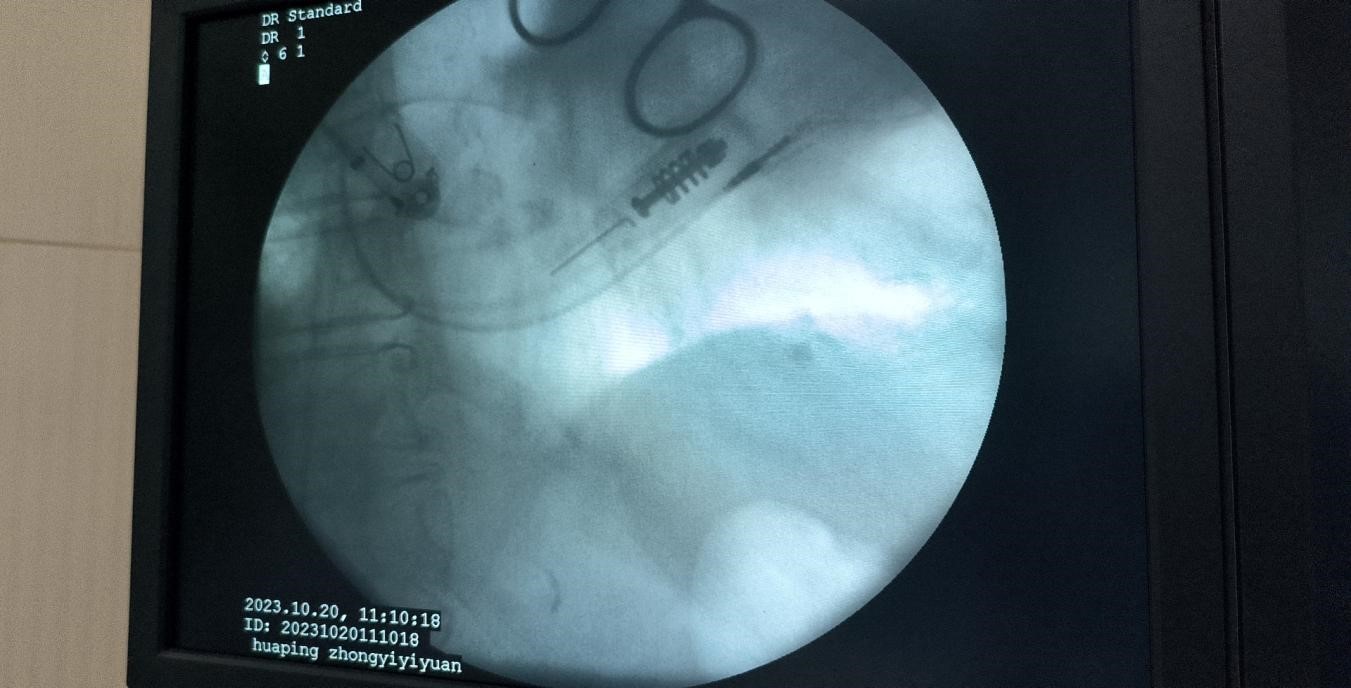

这次成功植入永久性心脏双腔起搏器的手术,对于华坪县中医医院来说是一次重要的突破。通过云南省中医医院专家团队的指导和支持,该院实现了在心脏起搏器植入领域的“零”的突破,为广大心血管疾病患者带来了福音。 这次手术的成功不仅展现了华坪县中医医院的医疗水平和技术实力,也标志着该院在心血管疾病治疗方面的进一步发展。未来,该院将继续开展各类疾病的介入治疗新技术,提高医疗水平,强化医疗服务能力,为保障人民健康做出更多贡献。 此次成功的植入手术对于高龄患者来说尤为重要,因为年龄较大的患者常常存在心脏功能下降、心律不齐等问题,需要进行心脏起搏器的植入治疗。通过此项手术的成功,不仅可以有效改善患者的心脏功能,还可以提升患者的生活质量。 华坪县中医医院将继续以高质量医疗服务为宗旨,为广大心血管疾病患者提供更加优质的治疗和护理,让群众的健康得到更好地保障。 |

这次成功的手术对于华坪县中医医院来说是一个里程碑式的突破。起搏器是一种治疗心脏疾病的重要设备,可以通过电信号来控制心脏的节律,对于一些心脏病变导致心律不齐的患者来说,起搏器是必不可少的。 而这次手术的成功,不仅意味着中医医院在心脏疾病治疗领域取得了新的突破,更为华坪县广大的心血管疾病患者带来了福音。以前,患者可能需要到其他医院进行手术,而现在在本地就能够得到高水平的治疗,无疑给患者减轻了很多负担。 这次手术的成功也表明,华坪县中医医院在医疗技术上的实力和水平逐渐提升。未来,该院将继续引进各类先进的治疗技术,为患者提供更好的医疗服务。同时,加强医疗服务能力建设,提高医疗人员的专业素质和技术水平,为守护人民健康做出更大的贡献。 总之,这次手术的成功是华坪县中医医院在心脏疾病治疗领域的重要突破,也为患者带来了福音。相信随着技术的不断进步和医院的不断发展,患者的幸福感会越来越强烈。 |